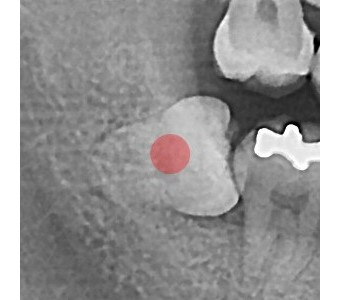

정확성 높은 치료의 시작 디지털 정밀진단 시스템

3D 디지털 데이터 기반으로 정확성 높고 정교한 치료가 가능합니다.

결과로 증명합니다.

국제모아치과의

실제 임상 증례